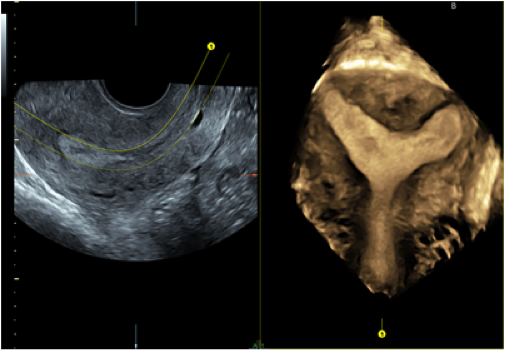

先日、超音波画像診断装置(※卵胞の大きさや内膜の厚さ、赤ちゃんの様子を確認する時に使う装置です)を入れ替えました。

今度の器械はGEヘルスケアジャパンのvoluson S10という超ハイペック機種です。

卵胞径、体積が自動計算できたり

子宮内宮の形が3Dで観察できたり

妊娠初期の赤ちゃんも3Dで観察できます。